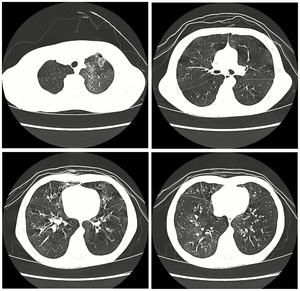

| High resolution CT scan showing bronchiolitis obliterans with mosaic attentuation, bronchiectasis, air trapping and bronchial thickening[3] | |

Medical imaging

Early in the disease chest radiography is typically normal but may show hyperinflation.[6] As the disease progresses a reticular pattern with thickening of airway walls may be present.[4][6] HRCT can also show air trapping when the person being scanned breathes out completely; it can also show thickening in the airway and haziness in the lungs.[11] A common finding on HRCT is patchy areas of decreased lung density, signifying reduced vascular caliber and air trapping.[6] This pattern is often described as a "mosaic pattern", and may indicate obliterative bronchiolitis.[6]